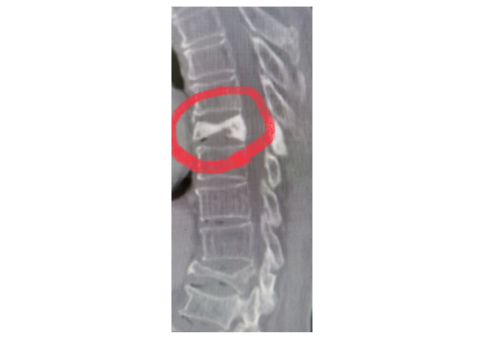

核磁检查示胸8椎体变扁(红圈位置),邻近胸7、胸9椎体可见不同程度骨质破坏